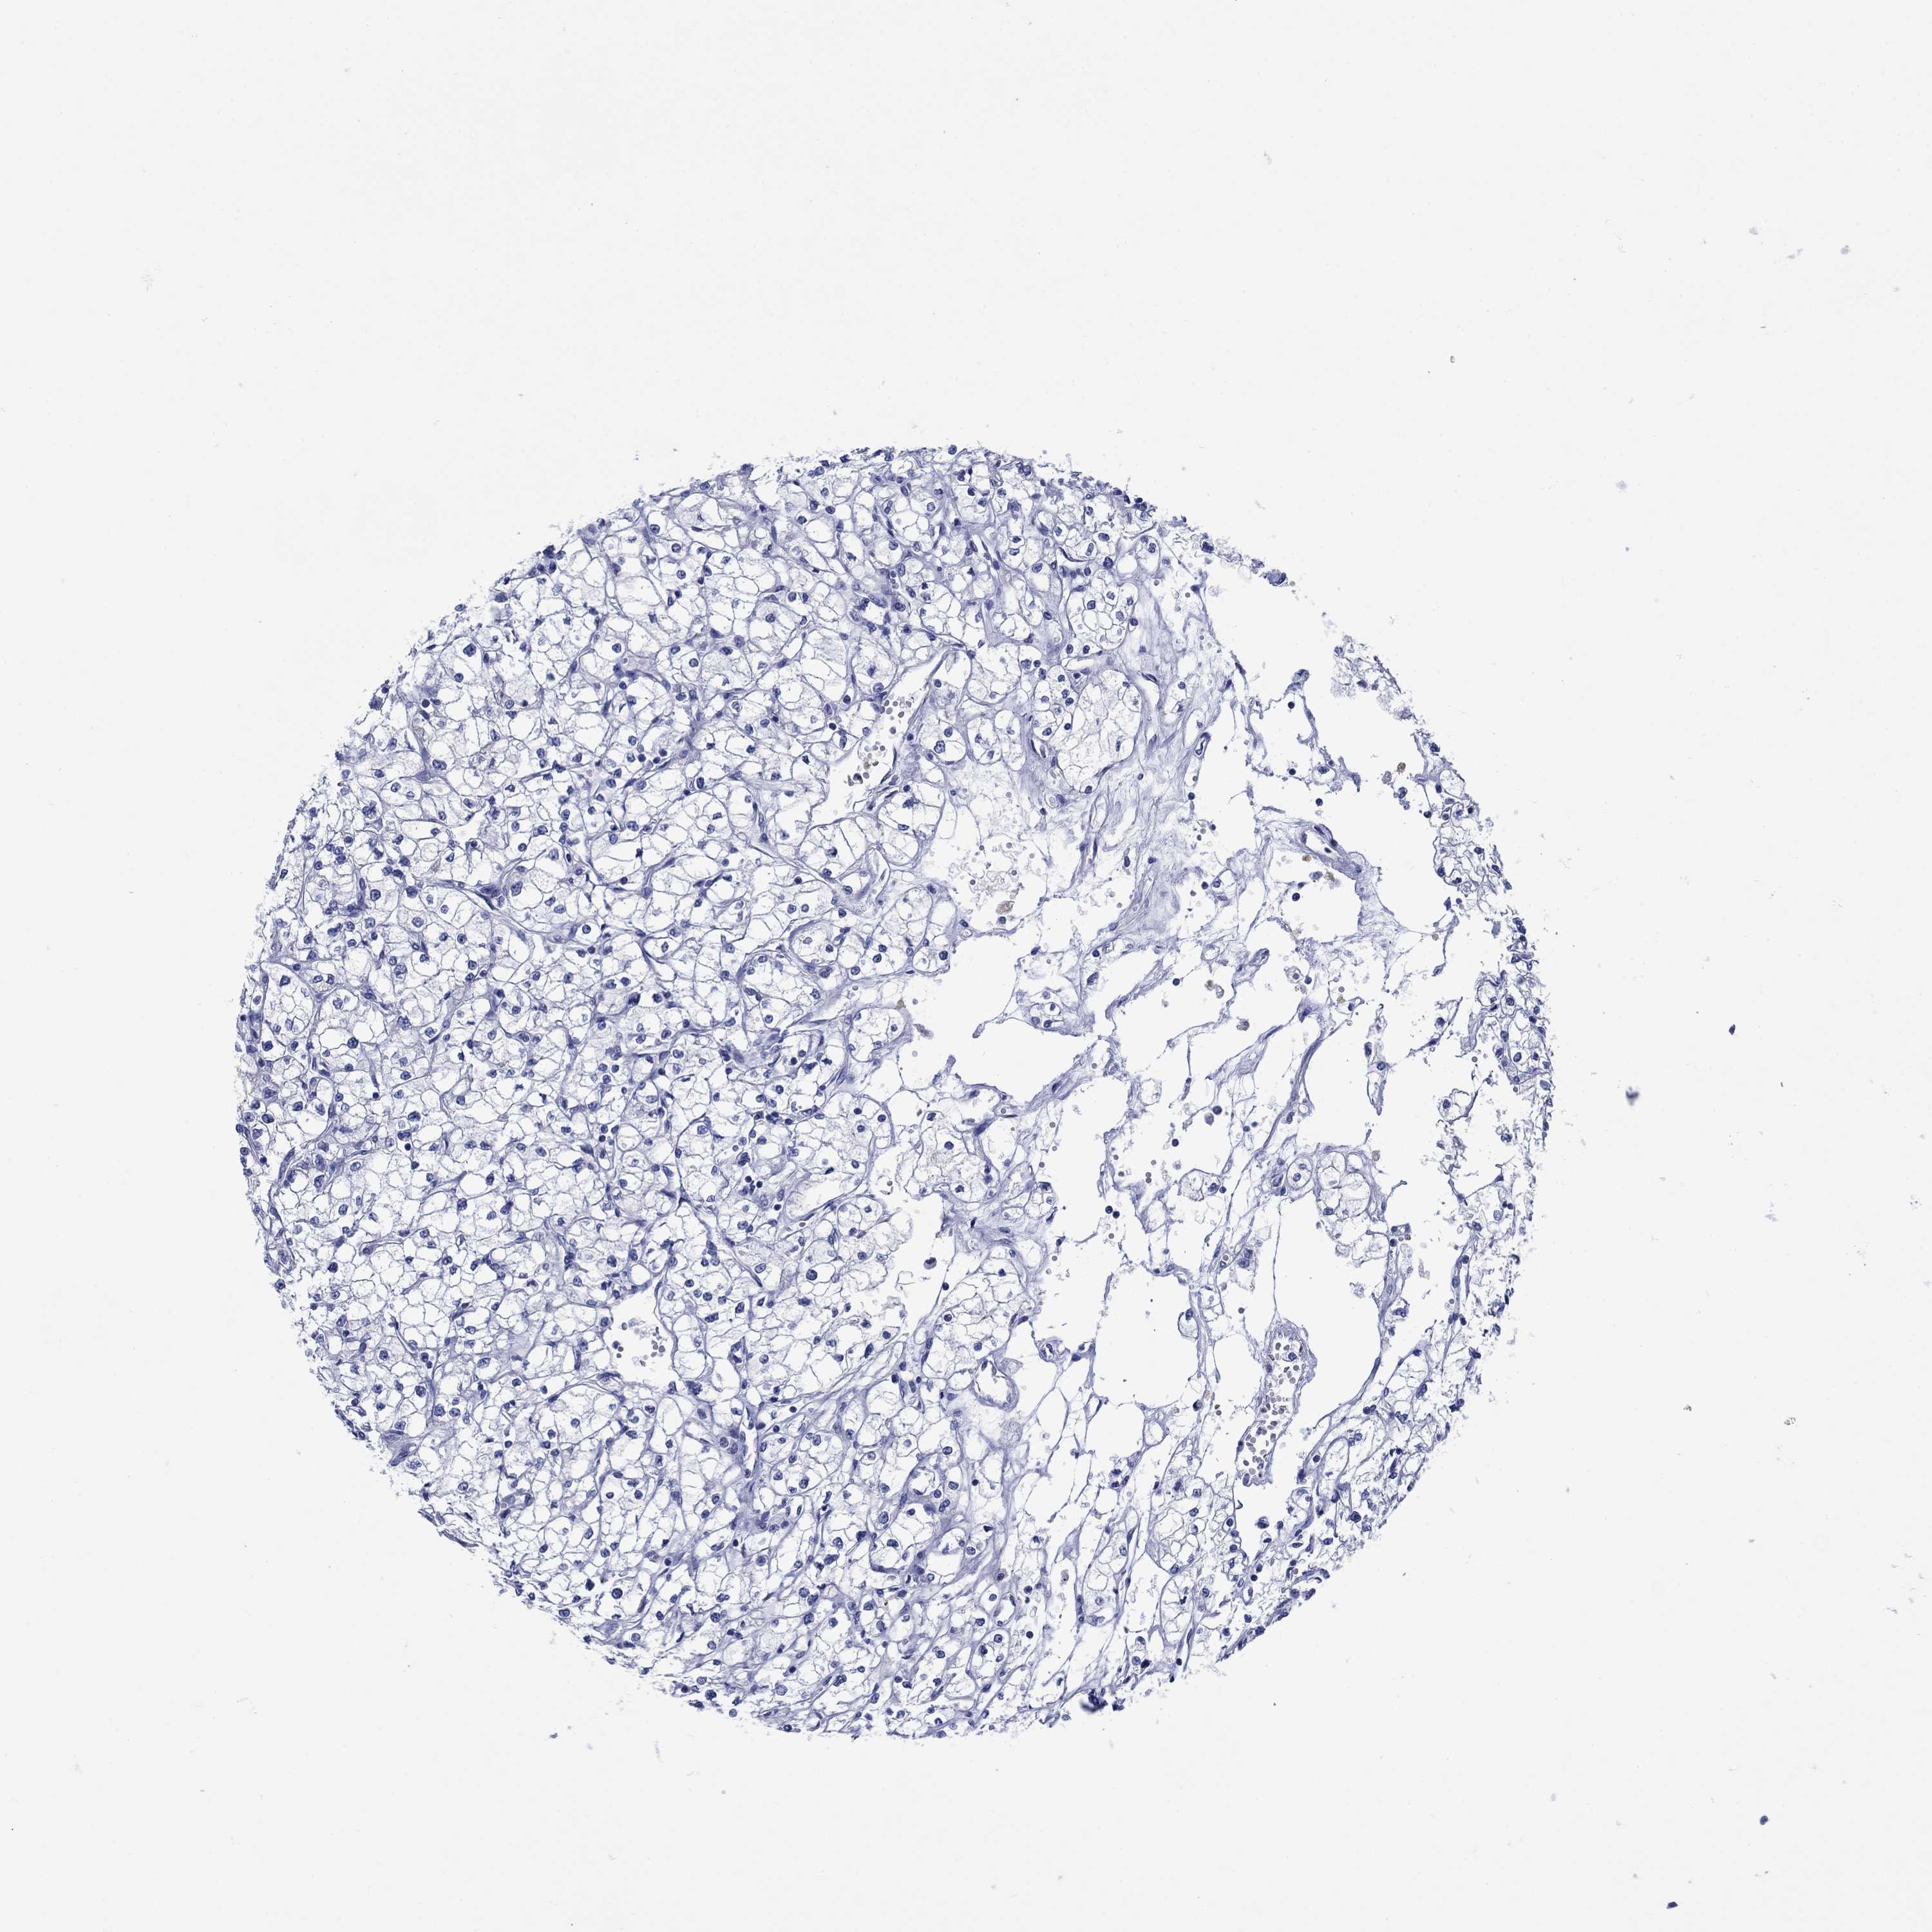

KIDNEY RENAL PAPILLARY CELL CARCINOMA (TCGA) - Interactive survival scatter ploti

The Survival Scatter plot shows the clinical status (i.e. dead or alive) for all individuals in the patient cohort, based on the same data that underlies the corresponding Kaplan-Meier plots. Patients that are alive at last time for follow-up are shown in blue and patients who have died during the study are shown in red.

The x-axis shows the expression levels (FPKM) of the investigated gene in the tumor tissue at the time of diagnosis. The y-axis shows the follow-up time after diagnosis (years). Both axes are complimented with kernel density curves demonstrating the data density over the axes. The top density plot shows the expression levels (FPKM) distribution among dead (red) and alive patients (blue). The right density plot shows the data density of the survived years of dead patients with high and low expression levels respectively, stratified using the cutoff indicated by the vertical dashed line through the Survival Scatter plot. This cutoff is automatically defined based on the FPKM cutoff that minimizes the p-score. The cutoff can be changed by dragging the vertical line or by entering a cutoff value in the square labeled "Current cut-off".

Under the Survival Scatter plot the p-score landscape (black curve; left axis) is shown together with dead median separation (red curve; right axis). Dead median separation is the difference in median mRNA expression between patients who have died with high and low expression, respectively. It is calculated as follows: median FPKM expression of dead patients with high expression - median FPKM expression of dead patients with low expression. This is intended to aid the user in visually exploring custom cutoffs and the associated p-scores and dead median separation.

Individual patient data is displayed and can be filtered by clicking on one or more of the category buttons on the top of the page. Categories describing expression level and patient information include: high, low, alive, dead, female, male and tumor stages. The scale of the x-axis can be toggled between linear and log-scale by clicking on the "x log" button. Mouse-over function shows TCGA ID, patient information and mRNA expression (FPKM) for each patient.

& Survival analysisi

Kaplan-Meier plots summarize results from analysis of correlation between mRNA expression level and patient survival. Patients were divided based on level of expression into one of the two groups "low" (under cut off) or "high" (over cut off). X-axis shows time for survival (years) and y-axis shows the probability of survival, where 1.0 corresponds to 100 percent.

TRIM16 is potential prognostic, high expression is unfavorable in Kidney Renal Papillary Cell Carcinoma (TCGA)